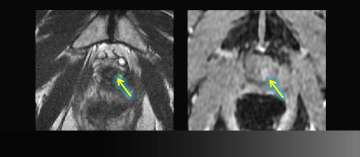

5) Extracapsular Extension and Seminal Vesicle Invasion by MRI + Spectroscopy and Pathology

Extracapsular Extension and Seminal Vesicle Invasion by MRI

• 59 year-old male

• PSA level: 10

• Clinical staging: T1C

• Blind systematic biopsy results: Gleason: 3+4=7 in the Left prostate

• Read More >